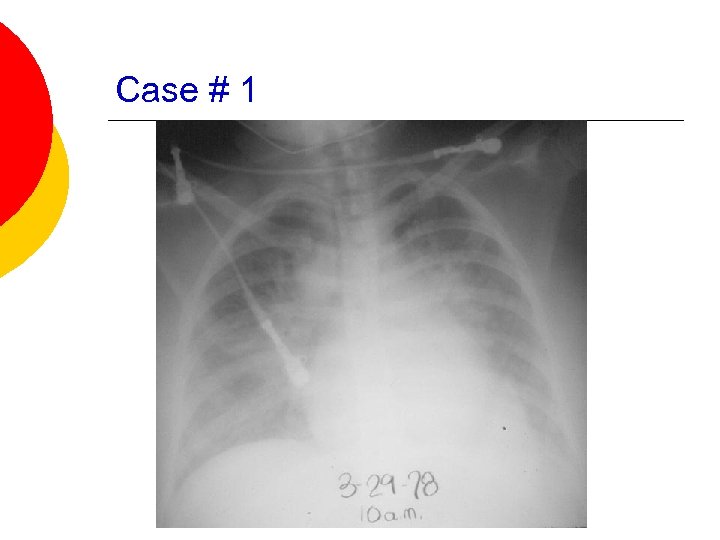

Case # 1 ¡ A 65 -year old male with a history of hypertension, DM, CAD s/p MI and threevessel CABG in 2002, presents with worsening dyspnea on exertion. He states that he occassionally has a dry cough, but denies any recent chest pain, fevers, N/V. Patient states that he usually can get up a flight of stairs if he stops half-way, but over the last several days, has not been able to climb them at all.

Case # 1 (cont. ) ¡ PMH: l l ¡ Allergies: l ¡ CAD – MI and CABG in 2002 Hypertension Diabetes Mellitus Hypothyroidism NKDA Outpatient Meds: l l l Synthroid Metformin Norvasc

Case # 1 (cont. ) ¡ Physical Exam: l l l 97. 6, 168/72, 99, 28, 93% on RA Gen: Alert and oriented x 3, breathing rapidly CV: RRR, no murmurs; mod. JVD Resp: Crackles throughout lungs Abd. : soft, nontender, NABS Ext: 2 + pitting edema bilaterally

Case # 1 (cont. ) ¡ Labs: l l l l Hgb: 13. 5 WBC: 8 Platelets: 240 Sodium: 139 Potassium: 3. 8 BUN: 18 Cr: 0. 8 l l Trop. I – 0. 01 CPK: 120

Case # 1

Case # 1 What studies would you like to check in this patient? ¡ What medications would you like to start/change? ¡ What vital signs do you want to monitor? ¡